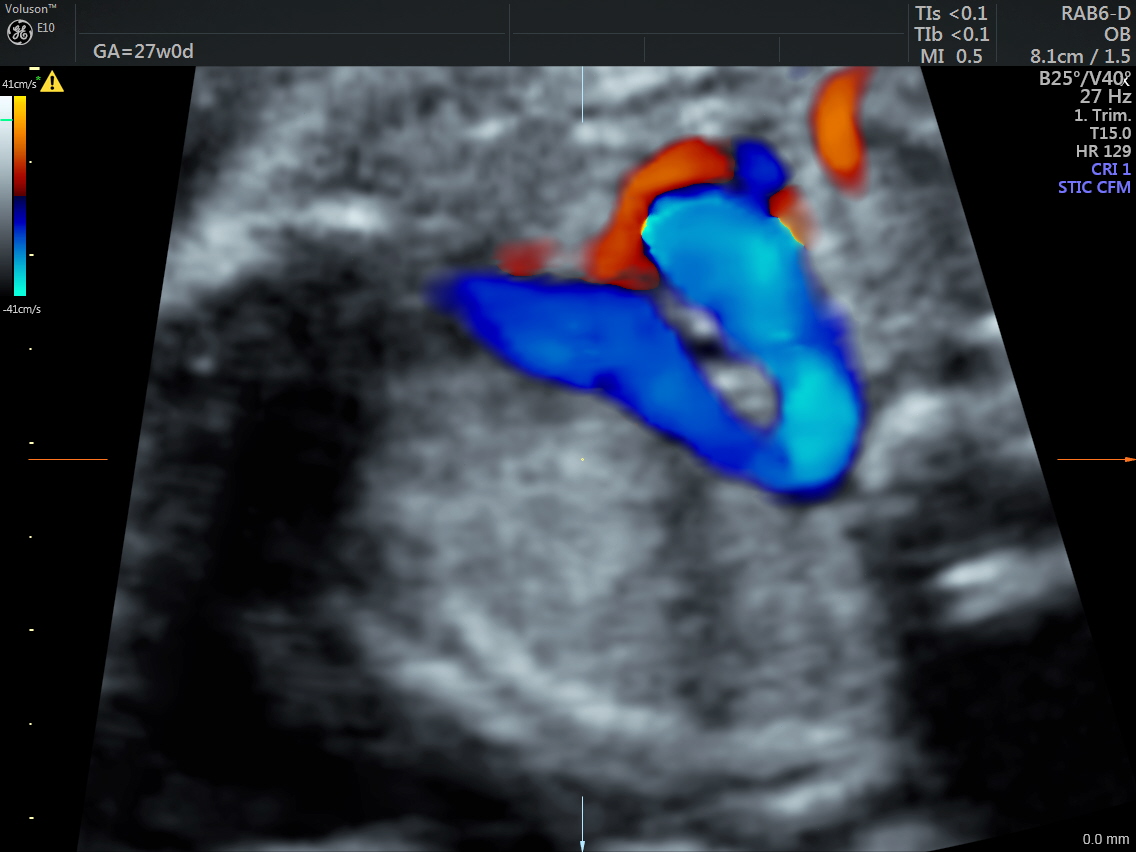

IMG_20160520_2_7 Published June 17, 2016 at 1136 × 852 in Rt aortic arch and aberrant left subclavian artery ← Previous Next →